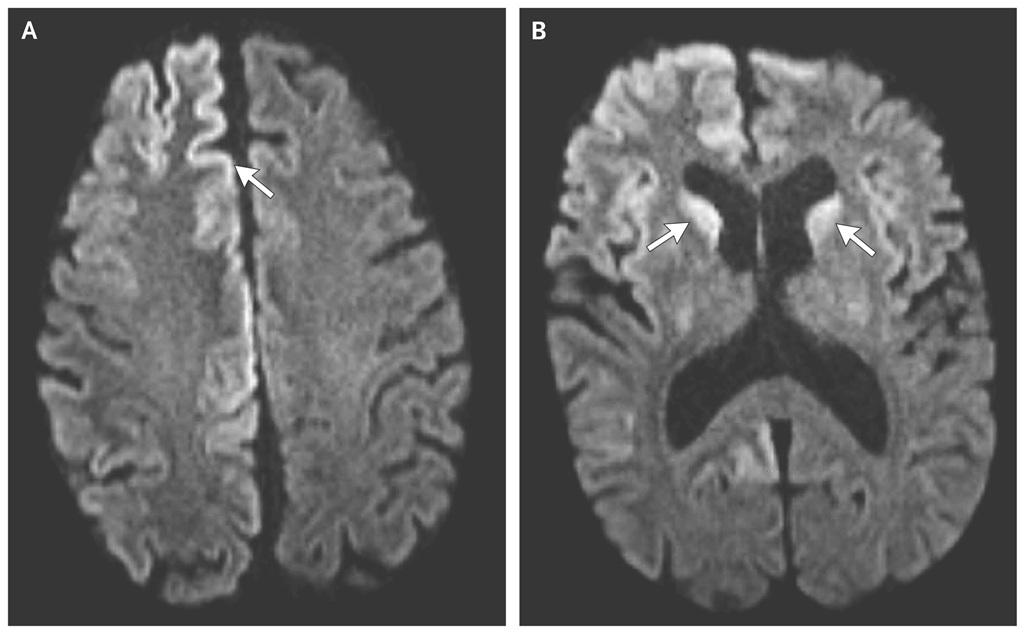

2. تشخیص زوال عقل: آزمایشهای تصویربرداری

پزشک شما ممکن است آزمایشهای تصویربرداری زیر را برای بررسی مغز شما تجویز کند:

- توموگرافی کامپیوتری (CT) و تصویربرداری تشدید مغناطیسی (MRI): CT از اشعه ایکس و یک کامپیوتر برای نمایش تصاویر دقیق از مغز شما استفاده میکند. MRI از آهنرباها، فرکانسهای رادیویی و کامپیوتر برای ایجاد تصاویر دقیق از مغز شما استفاده میکند. این آزمایشها برای یافتن شواهدی از سکته، خونریزی، تومورها و مایعات جمعشده در مغز انجام میشوند.